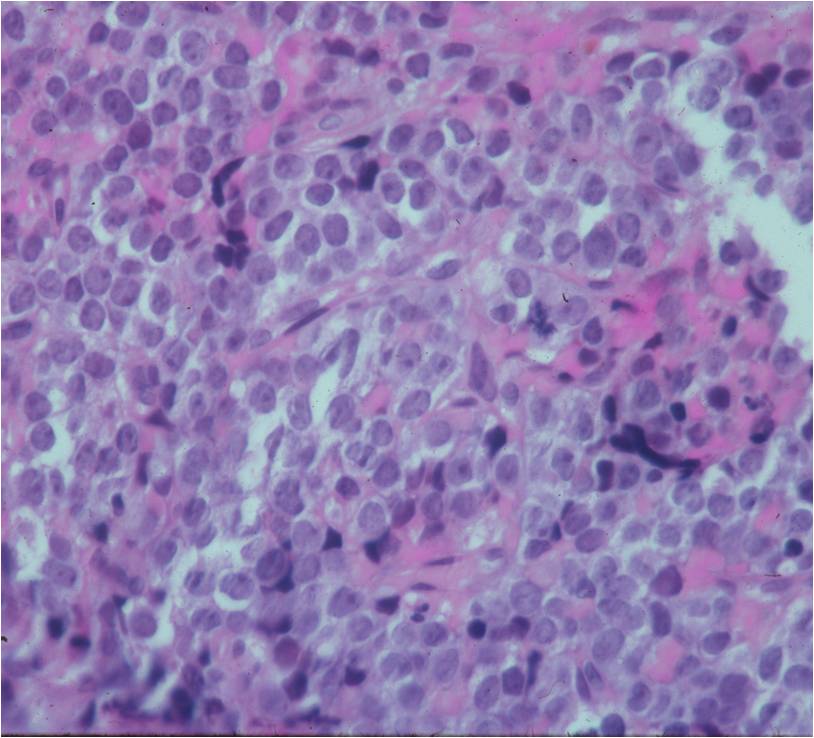

- Ewing sarcoma is composed of undifferentiated, small round, polygonal mesenchymal cells rich in glycogen

- Sheets of uniform cells with scanty pale cytoplasm and indistinct cell boarders

- No Matrix

- Nuclei are round/oval with finely dispersed chromatin

- Virtually no cytoplasm

- Areas of necrosis

- Variable number of mitoses

- Cells are similar in appearance

- Geographic necrosis with perivascular sparing

Small Round Blue Cells No Matrix Large Nuclei No Cytoplasm